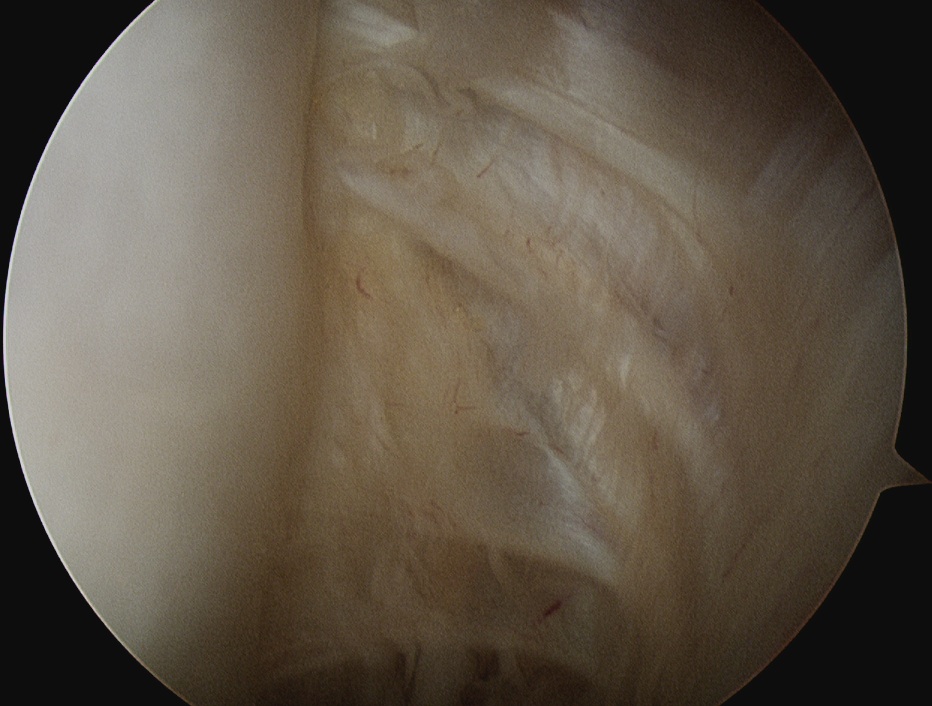

Shoulder arthroscopy

Rotator Interval - triangle of glenoid medial, biceps superior, subscapularis inferior

Humeral head cartilage

Glenoid cartilage

Labrum - anterior / inferior / posterior

Biceps tendon / insertion

Subscapularis

Glenohumeral ligaments

Three thickenings of the glenoid capsule: SGHL, MGHL, IGHL

| Superior glenohumeral ligament (SHGL) | Middle glenohumeral ligament (MGHL) |

|---|---|

|

Origin: Supraglenoid tubercle glenoid and coracoid Insertion: Proximal aspect medial edge lesser tuberosity of the humerus |

Origin: Distal aspect lesser tuberosity of humerus Insertion: Posterior aspect subscapularis |

Runs perpendicular to the middle GHL |

Crosses subscapularis vertically Variable size and shape in different people Cord like / leaf like / vestigal |

Stabilizes the long head of the biceps in its groove Limits external rotation of the humerus |

Limits external rotation with arm by side |

![]() |

| Inferior glenohumeral ligament (IGHL) | |

Origin: Inferior 2/3 glenoid and labrum Insertion: Anatomical neck humerus

Anterior band: antero-inferior glenoid to 3 o'clock Posterior band: postero-inferior glenoid to 9 o'clock Axillary pouch between two bands |

| Most important ligament in terms of stability | Stabilizes arm at 90 degrees of abduction |